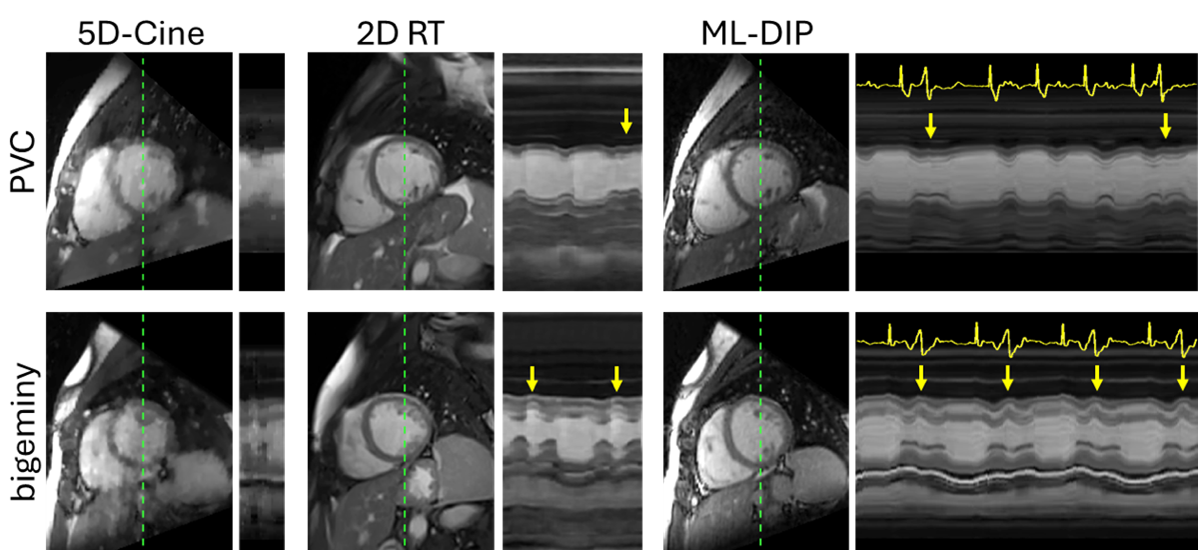

Figure 2: Representative short-axis images from 5D-cine, 2D RT, and ML-DIP. Space-time (x-t) profiles along the dashed green lines are shown to the right of the images. The ML-DIP x–t profiles span 200 frames (6.6 s), while the x-t profiles span 3 seconds for 2D RT cine and one cardiac cycle for 5D-Cine. The 3D reconstructions from 5D-Cine and ML-DIP were interpolated along the 2D plane defined by the 2D RT acquisition. Significant motion artifact is observed in 5D-Cine. The arrows indicate PVC beats. The synchronous ECG is plotted in yellow.